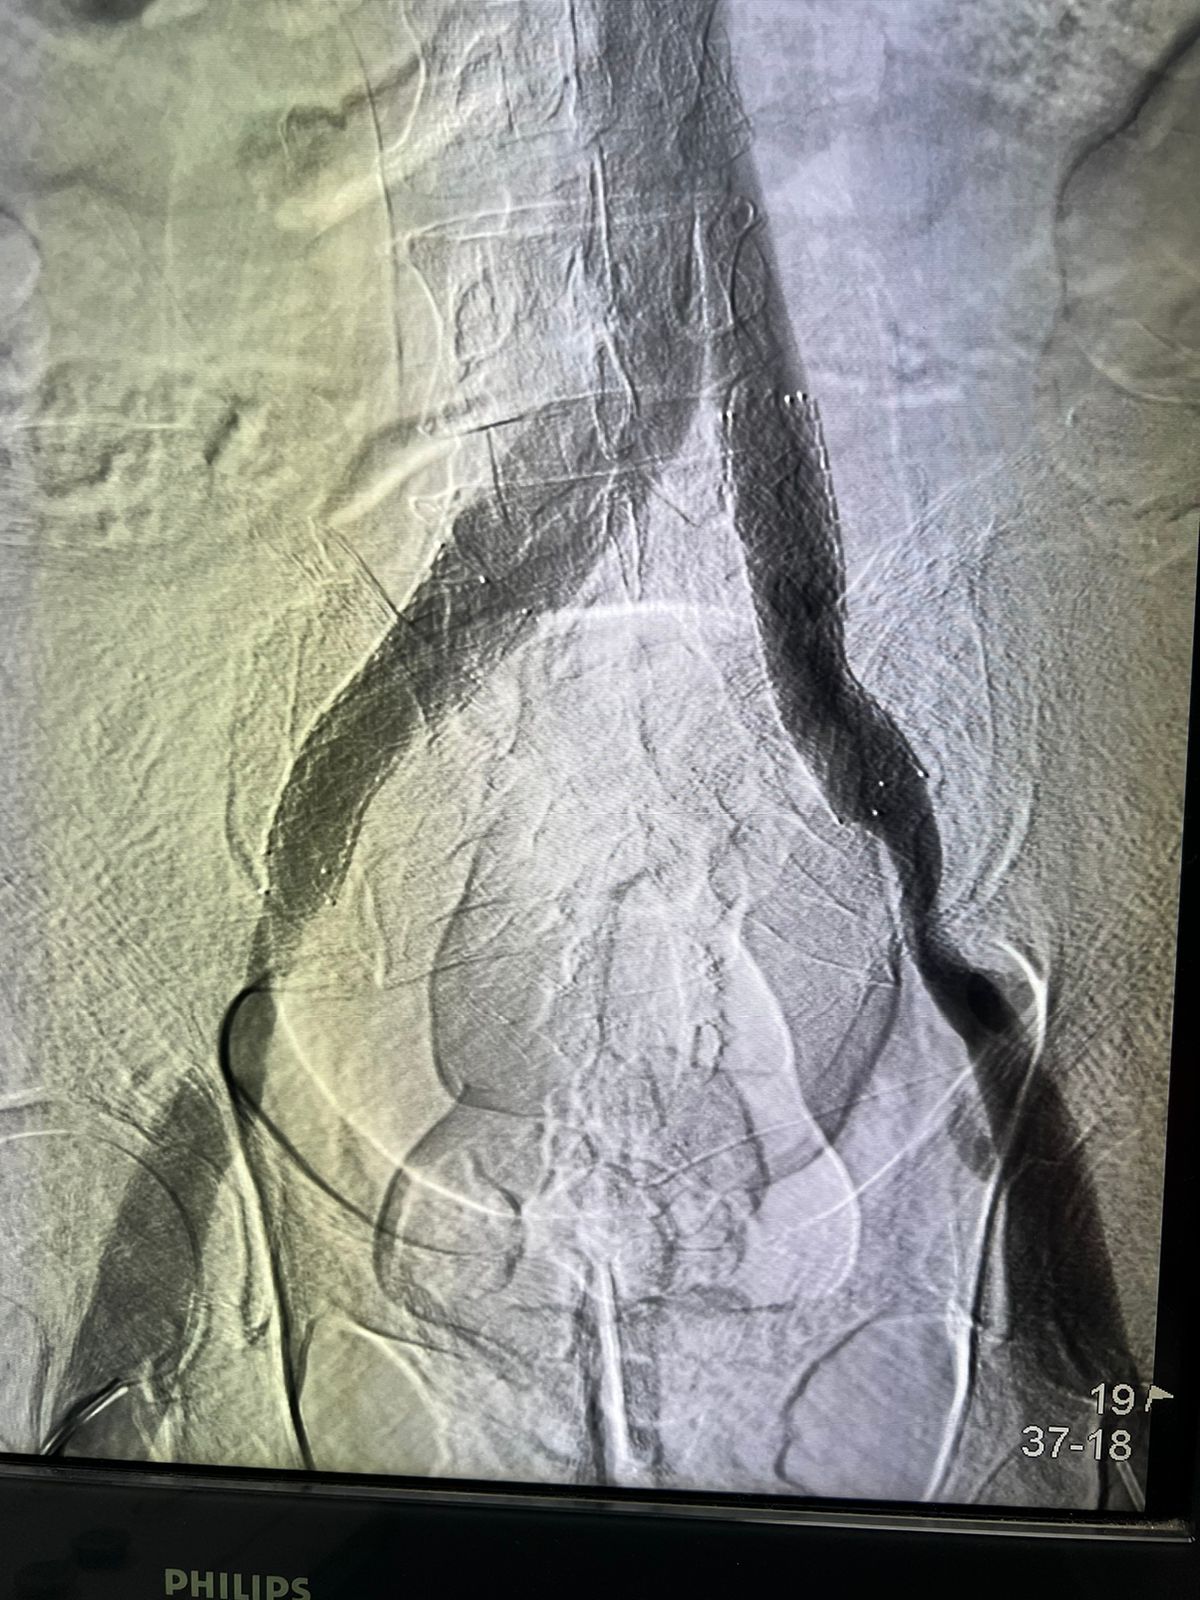

Flebografía (Cateterismo)

Procedimientos mínimamente invasivos realizados a través de punciones en las venas. Con el uso de dispositivos especiales, como catéteres, ultrasonido, stents y sistemas para la infusión de medicamentos, se busca tratar venas afectadas por cicatrices y trombosis. Estos procedimientos permiten mejorar el flujo venoso y, en casos de trombosis venosa profunda, extraer los coágulos para prevenir complicaciones graves.